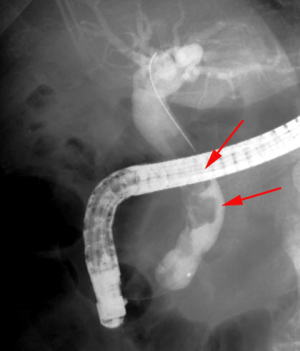

【EPLBD】 |

総胆管に15mm大の胆管結石を2個認めています(矢印)。 |

口径15~18mmの大口径拡張バルーンを用いて十二指腸乳頭(胆管の出口)の拡張術を実施しました。 |

矢印の間が拡張バルーンです。 |

乳頭拡張後に採石用のバスケット(金属線の器具)を用いて結石を破砕することなく除去しました。 |

除去した結石です。この方法では結石を破砕しなくて済むため、1回の処置でほぼすべての結石を除去することができます。 |